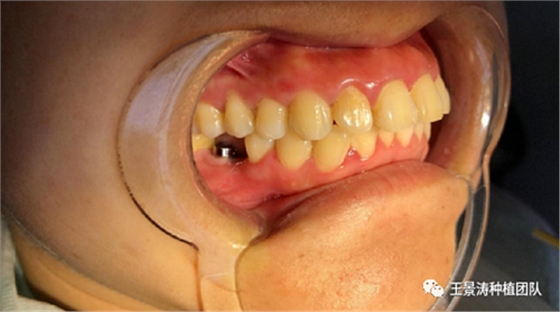

左側(cè)下頜第二磨牙及右側(cè)下頜第一磨牙同時(shí)即刻種植病例?;颊吣贻p女性,無系統(tǒng)性疾病。37及46殘冠及殘根,且46劈裂,無法冠修復(fù),必須拔除。37根尖慢性炎癥,大量肉芽組織存在,46根分叉較高,根分叉骨質(zhì)尚可。CBCT示:根尖骨質(zhì)至下牙槽神經(jīng)管距離可滿足種植體的初期穩(wěn)定性,遂考慮即刻種植,并在種植體周邊填入骨粉并覆蓋骨膜,雙側(cè)的種植體初期穩(wěn)定性相差無幾,但考慮到37根尖慢性炎癥較大,遂給予埋入式種植。

術(shù)后一周的口內(nèi)照片